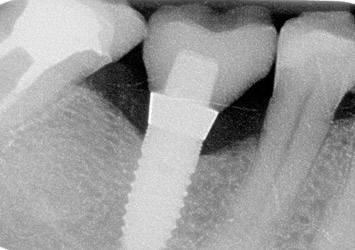

Cas 6 : 2 molaires et 1 prémolaire inférieure

Couronne et inlay-core sur dent + Couronne sur implant + Incrustation